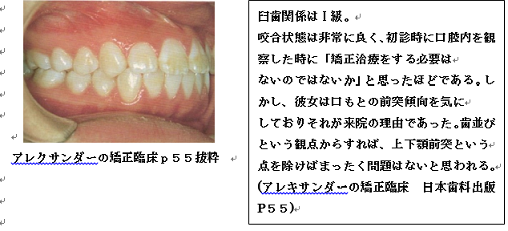

前回は左の写真(上顎前突)を説明しました。今回は右の写真を説明していきたいと思います。

歯・口腔の健康診断パネル③ 抜粋 アレクサンダーの矯正臨床p55抜粋

20世紀の最高峰の矯正医アレクサンダー先生が完全な個性正常咬合であると認めている

歯並びに対して口もとが前突気味だと言うだけで患者さんの主訴(同意)もかえりみず抜歯をすることが頭に浮かんでしまう矯正医が少なからずいます。

今回の症例は患者さんの強い主訴があるためにアレクサンダー先生は抜歯矯正処置を行いました。

歯・口腔の健康診断パネル③ 抜粋 アレクサンダーの矯正臨床p55抜粋